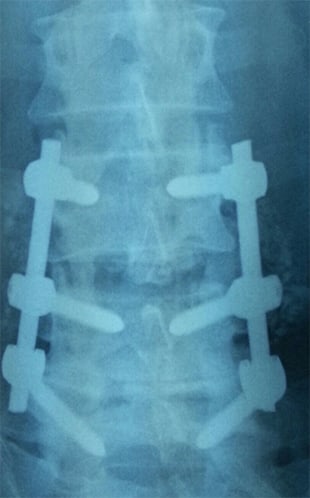

- Intrasite Vancomycin powder as a prophylactic adjuvant in lumbar fusión.

- Coluna/Columna 2016;15(1):44-47 Ver Artículo

- Vancomicina transtisular en polvo como adyuvante en profilaxis antibiótica en fusión lumbar Ver PDF